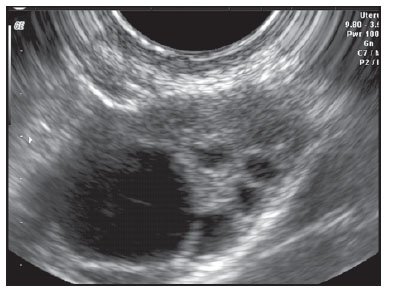

Симптомите на ендометриозата включват болка, проблеми с плодовитостта, нередовни менструални цикли, болка по време на половия акт, болка при уриниране и дефекация, кръв в урина или изпражнения и запек. Може да причини симптоми като болки по време на овулация, предменструален синдром и други неприятни проблеми. Може да доведе до образуване на ендометриозни кисти, които могат да се спукат, причинявайки болка и разпространение на ендометриоза в други области на тялото. Освен това може да доведе до сраствания и лезии, засягащи яйчниците и фалопиевите тръби, както и намалявайки репродуктивната функция. Освен това може да доведе до проблеми със зачеването и бременността.

Причината за ендометриозата не е известна, но се смята, че може да възникне на фон на хронични инфекции като хламидия или други подобни заболявания. Диагностицирането на ендометриоза се извършва чрез лапарскопия, която позволява визуализиране и отстраняване на увредените участъци. Хистероскопията не е достатъчна за диагностициране на ендометриоза, тъй като тя може да се развие извън матката. Ендометриозата се диагностицира чрез лапароскопия, която е основният метод за диагностика. Освен това може да се използва и трансвагинална лапароскопия, където достъпът е през влагалището.